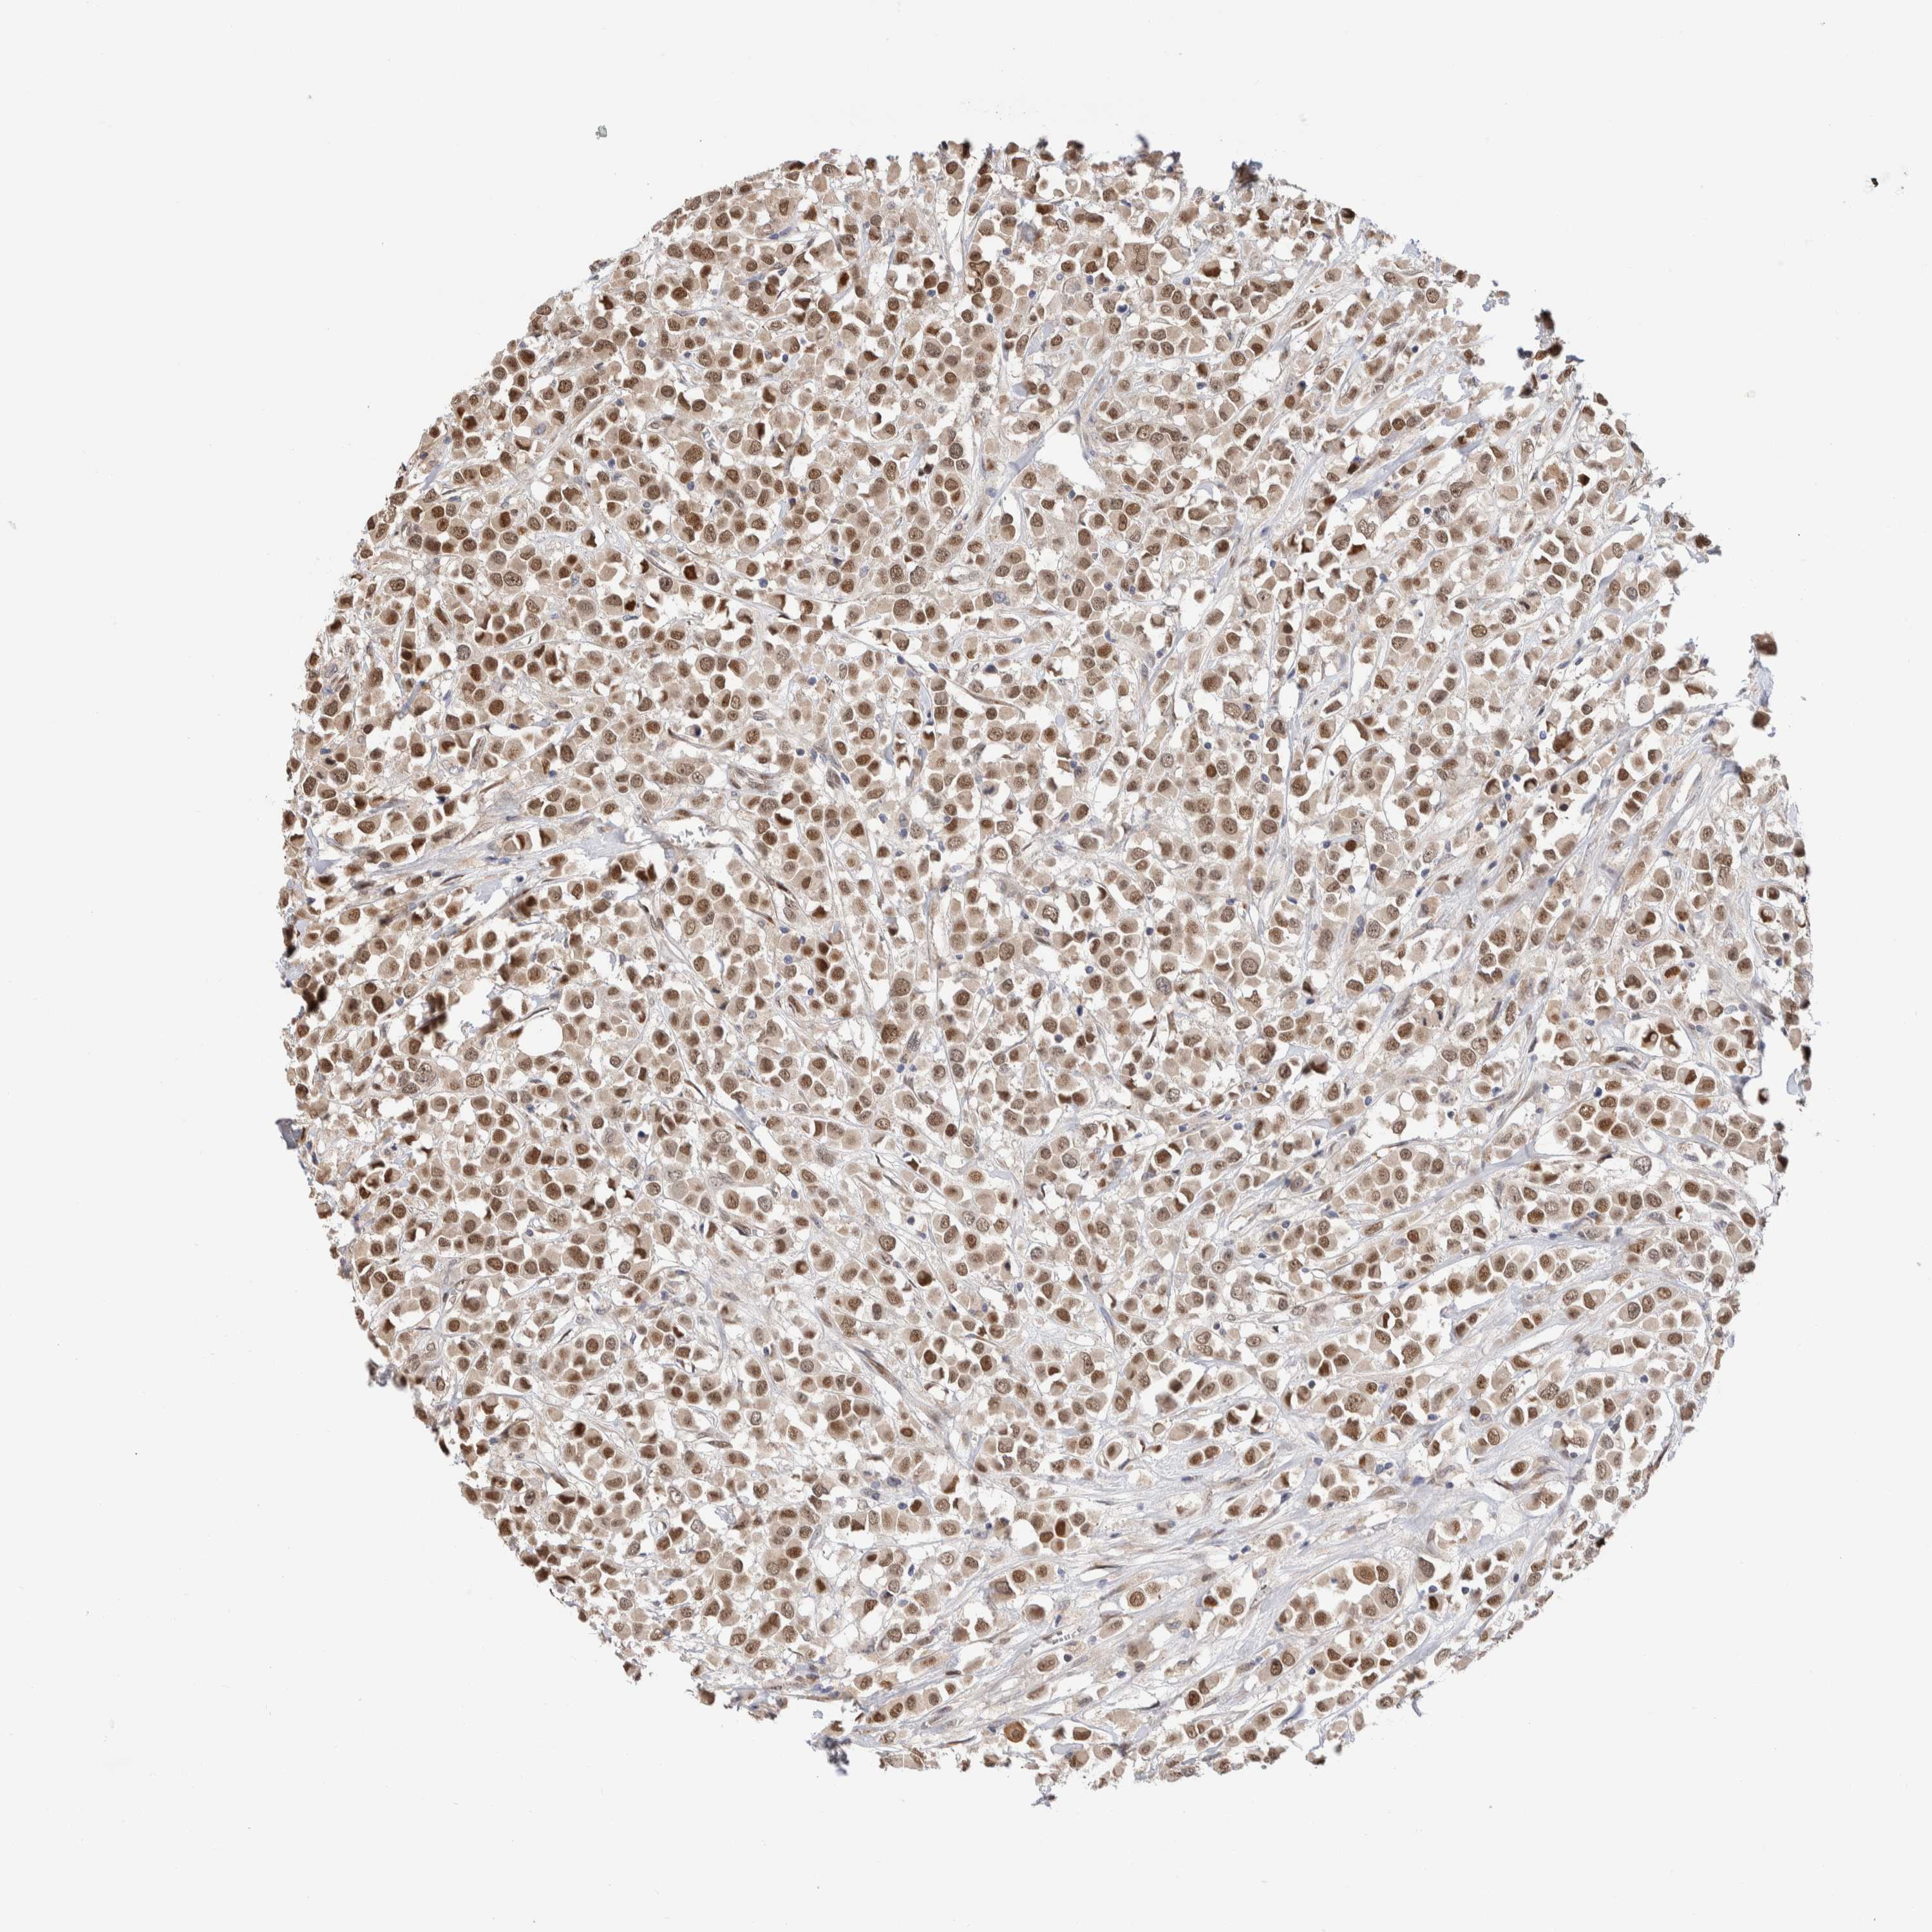

CANCER BREAST CANCER Show tissue menu

BRCA TCGA BRCA VALIDATION PROTEIN EXPRESSION